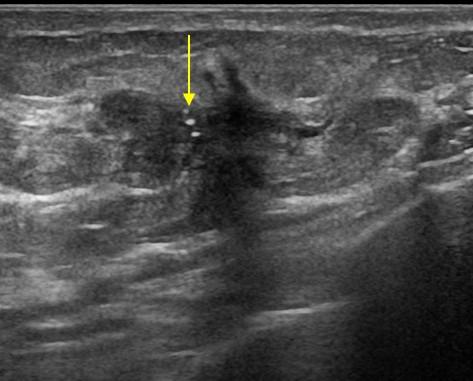

Ung thư vú

» Thông tin: Nữ giới – 52 tuổi.

» Lâm sàng: Khối tuyến vú.